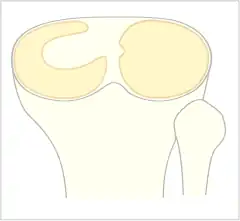

The Watanabe classification of discoid lateral meniscus is: (A) Incomplete, (B) Complete, and C) Wrisberg-ligament variant [2] Normally, the meniscus is a thin crescent-shaped piece of cartilage that lies between the weight bearing joint surfaces of the femur and the tibia. It is attached to the lining of the knee joint along its periphery and serves to absorb about a third of the impact load that the joint cartilage surface sees and also provides some degree of stabilization for the knee. There are two menisci in the knee joint, with one on the outside (away from midline) being the lateral meniscus and the inner one (towards midline) the medial meniscus. A discoid meniscus is a congenital anomaly of the knee found in 3% of the population (up to 15% in Asia). It typically affects the lateral meniscus and may be found bilaterally (20%). Instead of the narrow crescent shape, as seen in a normal meniscus above, a discoid meniscus is thickened, and has a fuller crescent shape. In addition, a discoid meniscus does not taper as much towards the center of the joint and is shaped like a disc. The thickness of the meniscus, its diminished vascular blood supply, and in some instances, weak capsular attachment, makes it more prone to tears compared to a normal meniscus. The anomaly in itself is asymptomatic; however, a tear of the meniscus can result in pain, swelling, and snapping in the affected knee. The orthopedic classification of discoid menisci includes: complete, incomplete or Wrisberg-ligament types as depicted here. Coverage of the lateral tibial plateau determines the designation of complete or incomplete. The Wrisberg-ligament type has an abnormal posterior attachment by attaching to part of the posterior cruciate ligament.